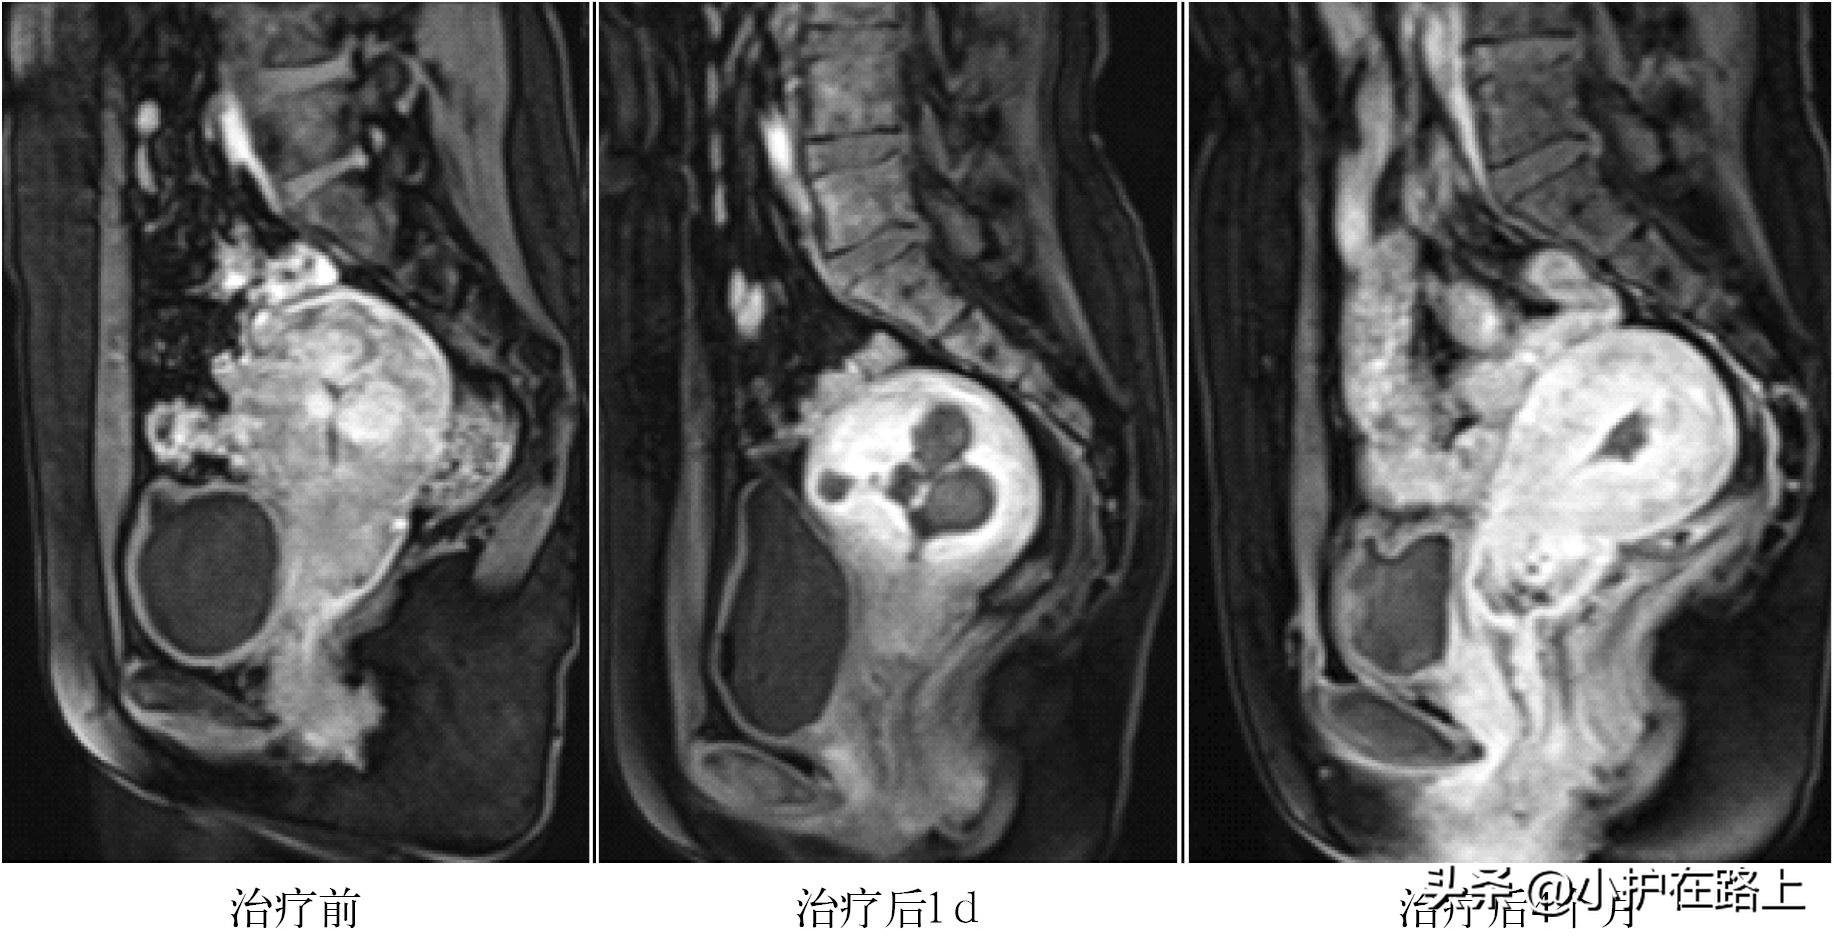

聚焦超声消融手术子宫肌瘤的原理:以超声波为能量源,利用超声波在人体的良好穿透性,将HIFU换能器产生的超声波聚焦于子宫肌瘤病灶内,通过超声波产生的热效应、机械效应、空化效应,在影像超声的监控下,准确消融目标肌瘤。由于治疗时仅在焦点处产生瞬间高热量,因此,仅毁损靶区子宫肌瘤组织,而对超声能量经过的组织不造成损伤。HIFU治疗后,坏死的肌瘤逐渐被吸收,肌瘤缩小,子宫结构恢复正常(见图1)。

图1 多发子宫肌瘤HIFU治疗后的影像学变化